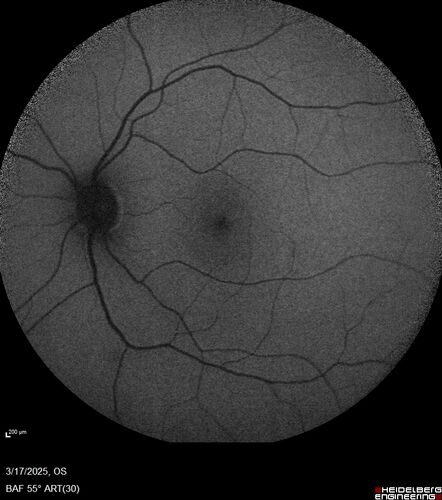

Optic Neuritis sentinel event for MS (23 year old female)

23-year-old female contact lens wearer reports recurrent blurry vision with a central "blob" in the right eye, first occurring in December 2024 for two weeks, then briefly affecting the left eye, and now recurring in the right eye. Symptoms have been painless, with no eye movement discomfort or neurological changes.

VA: OD 20/40 PH 20/30; OS 20/25

IOP: OD 17, OS 18